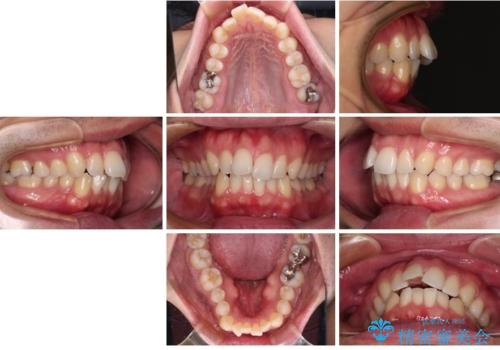

- 口元の突出感と下の前歯のがたつきを主訴として来院された患者様です。

口元の突出感と叢生改善のため上下左右の第一小臼歯4本を抜歯し、ワイヤー装置にて矯正治療を行うこととしました。

なるべく目立たない装置が希望だったため、審美装置で治療を行いました。

左上はアンカースクリューを併用することでスムーズに抜歯スペースを閉じることができました。

口元の突出感もなくなり満足されました。